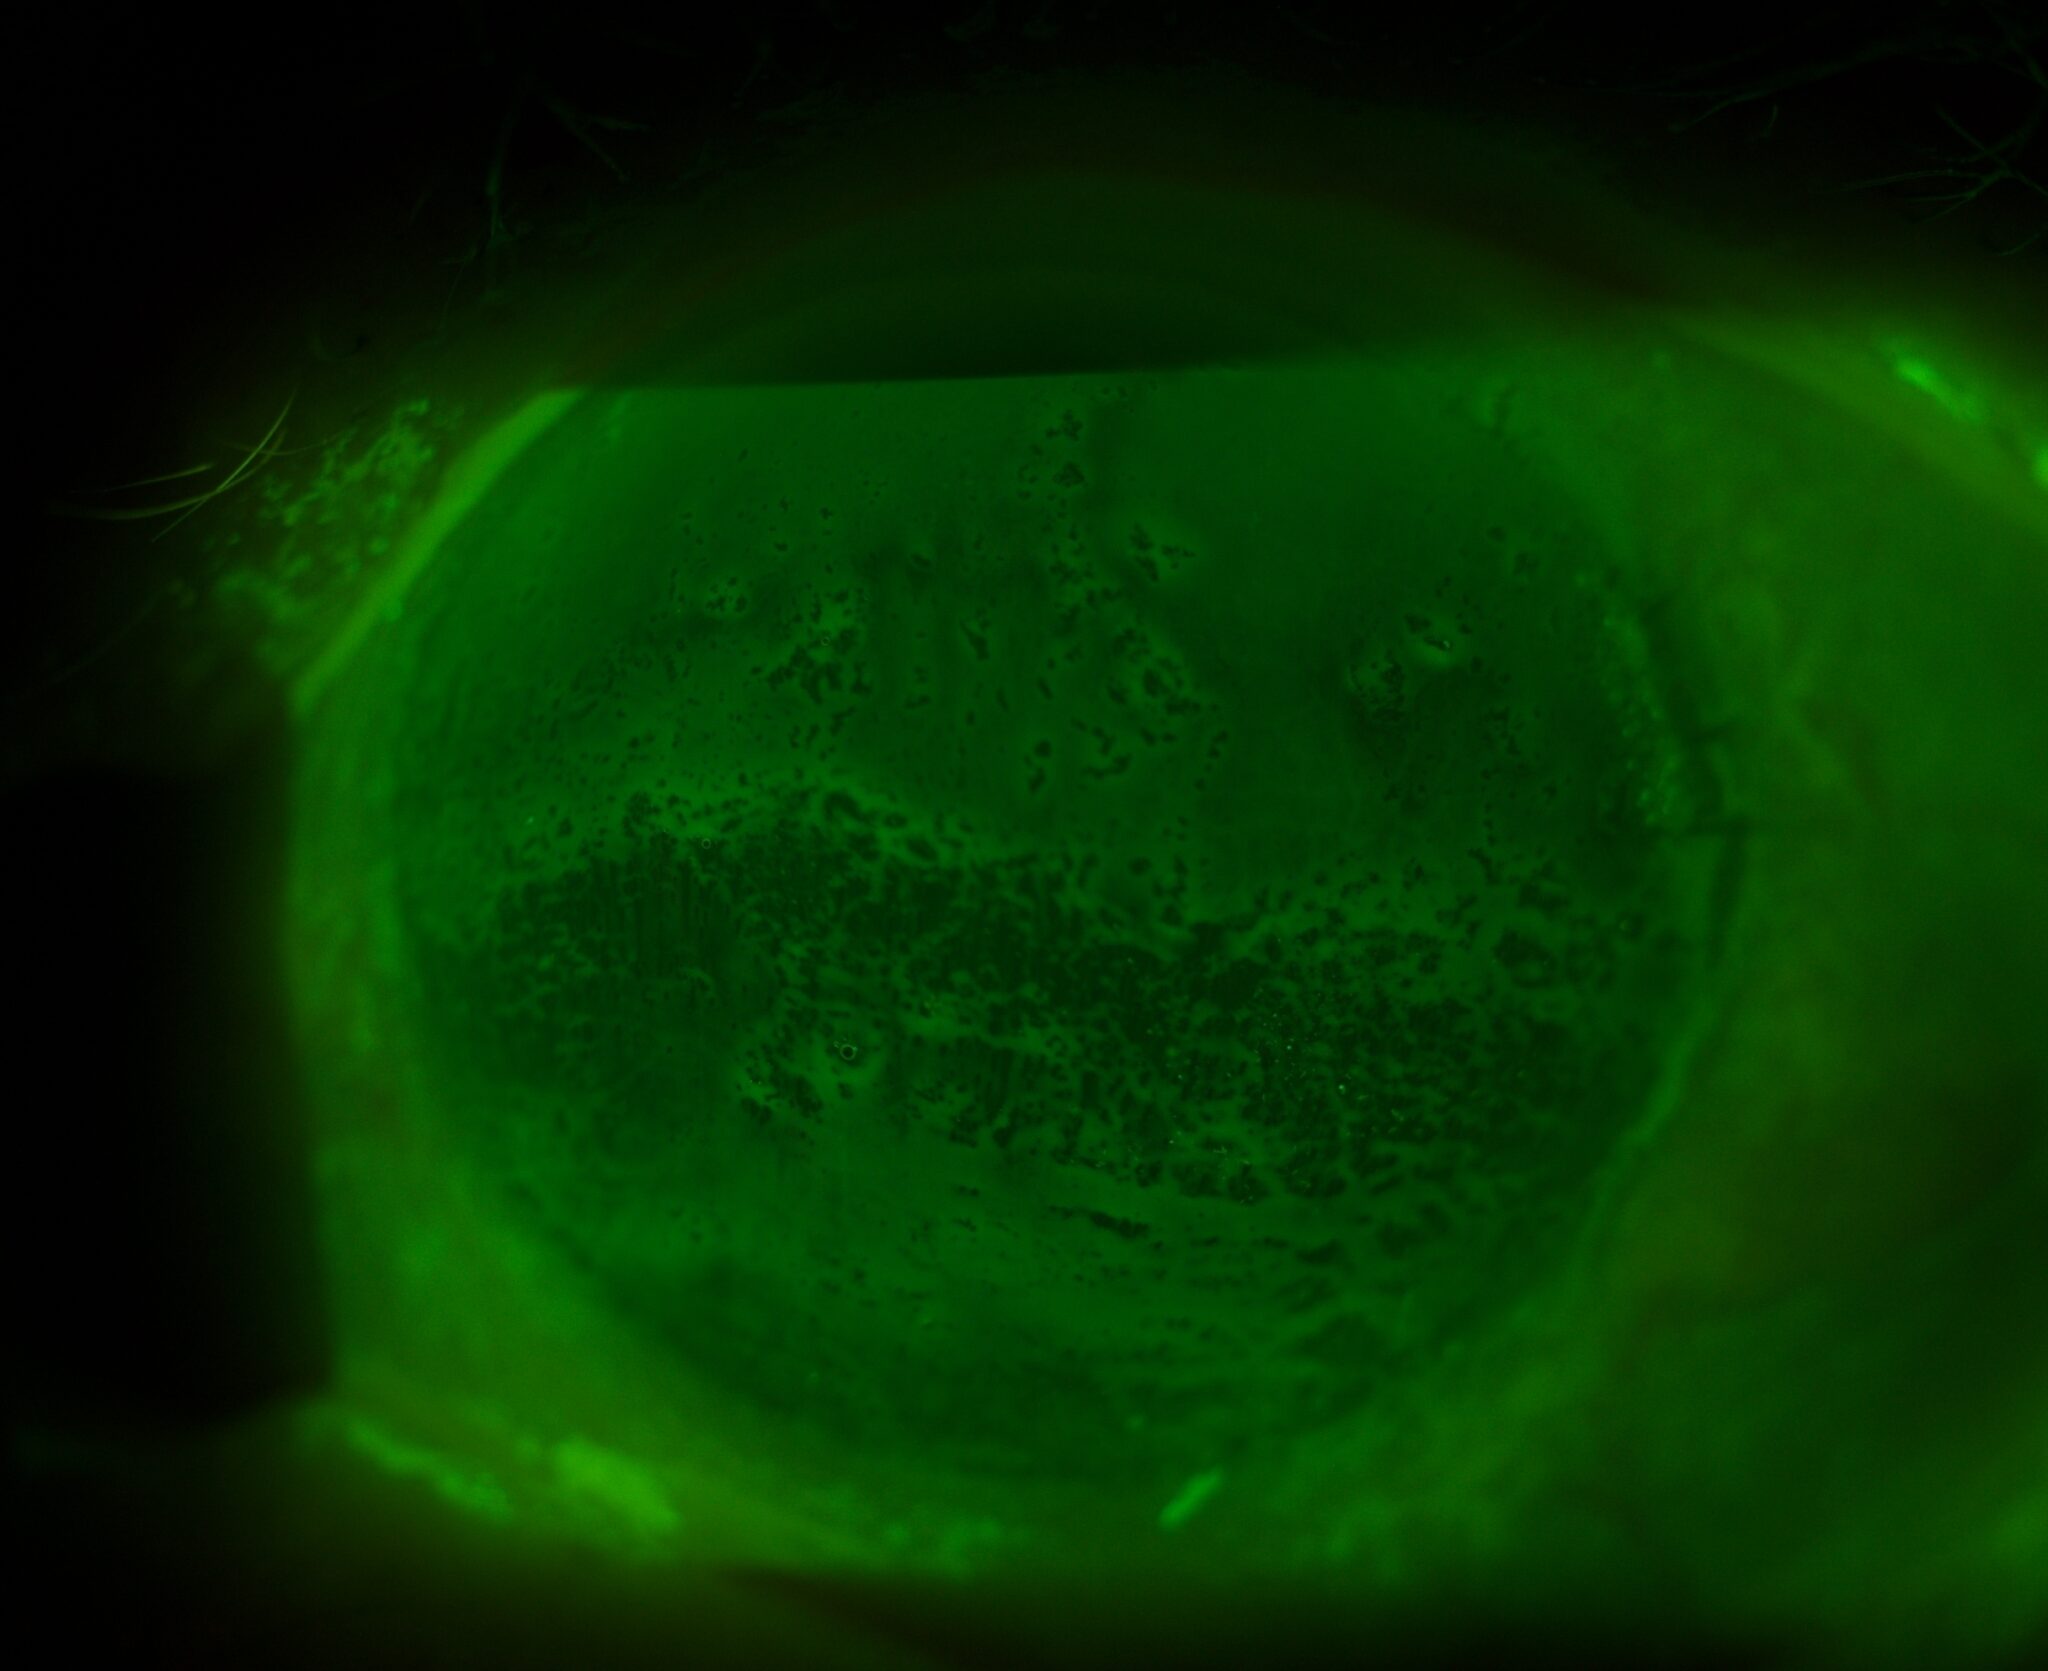

Whether assessing the anterior or posterior segment or working under unfavorable light conditions – benefit from a view that is both natural and high in contrast. Elara 900’s Galilean microscope – with its five-step magnification range from 6.3x up to 40x – unveils more detail with every turn.

Elara 900’s revolutionary projector light source (“P-Type”) can emit colors across the entire visible spectrum, allowing different color temperatures to be selected for individual pathologies. Offering more illumination modes than traditional LED or halogen sources, the result is a high-resolution, high-contrast examination that aids in the identification of ocular structures. Infrared* illumination enables seamless Meibomian gland assessment, further boosting your workflow.